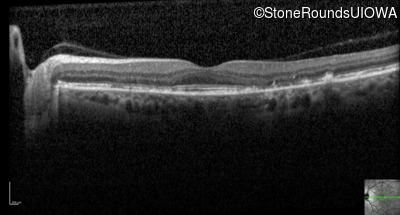

Optical Coherence Tomography - Right - 20/20

Exemplar / OCT Stack